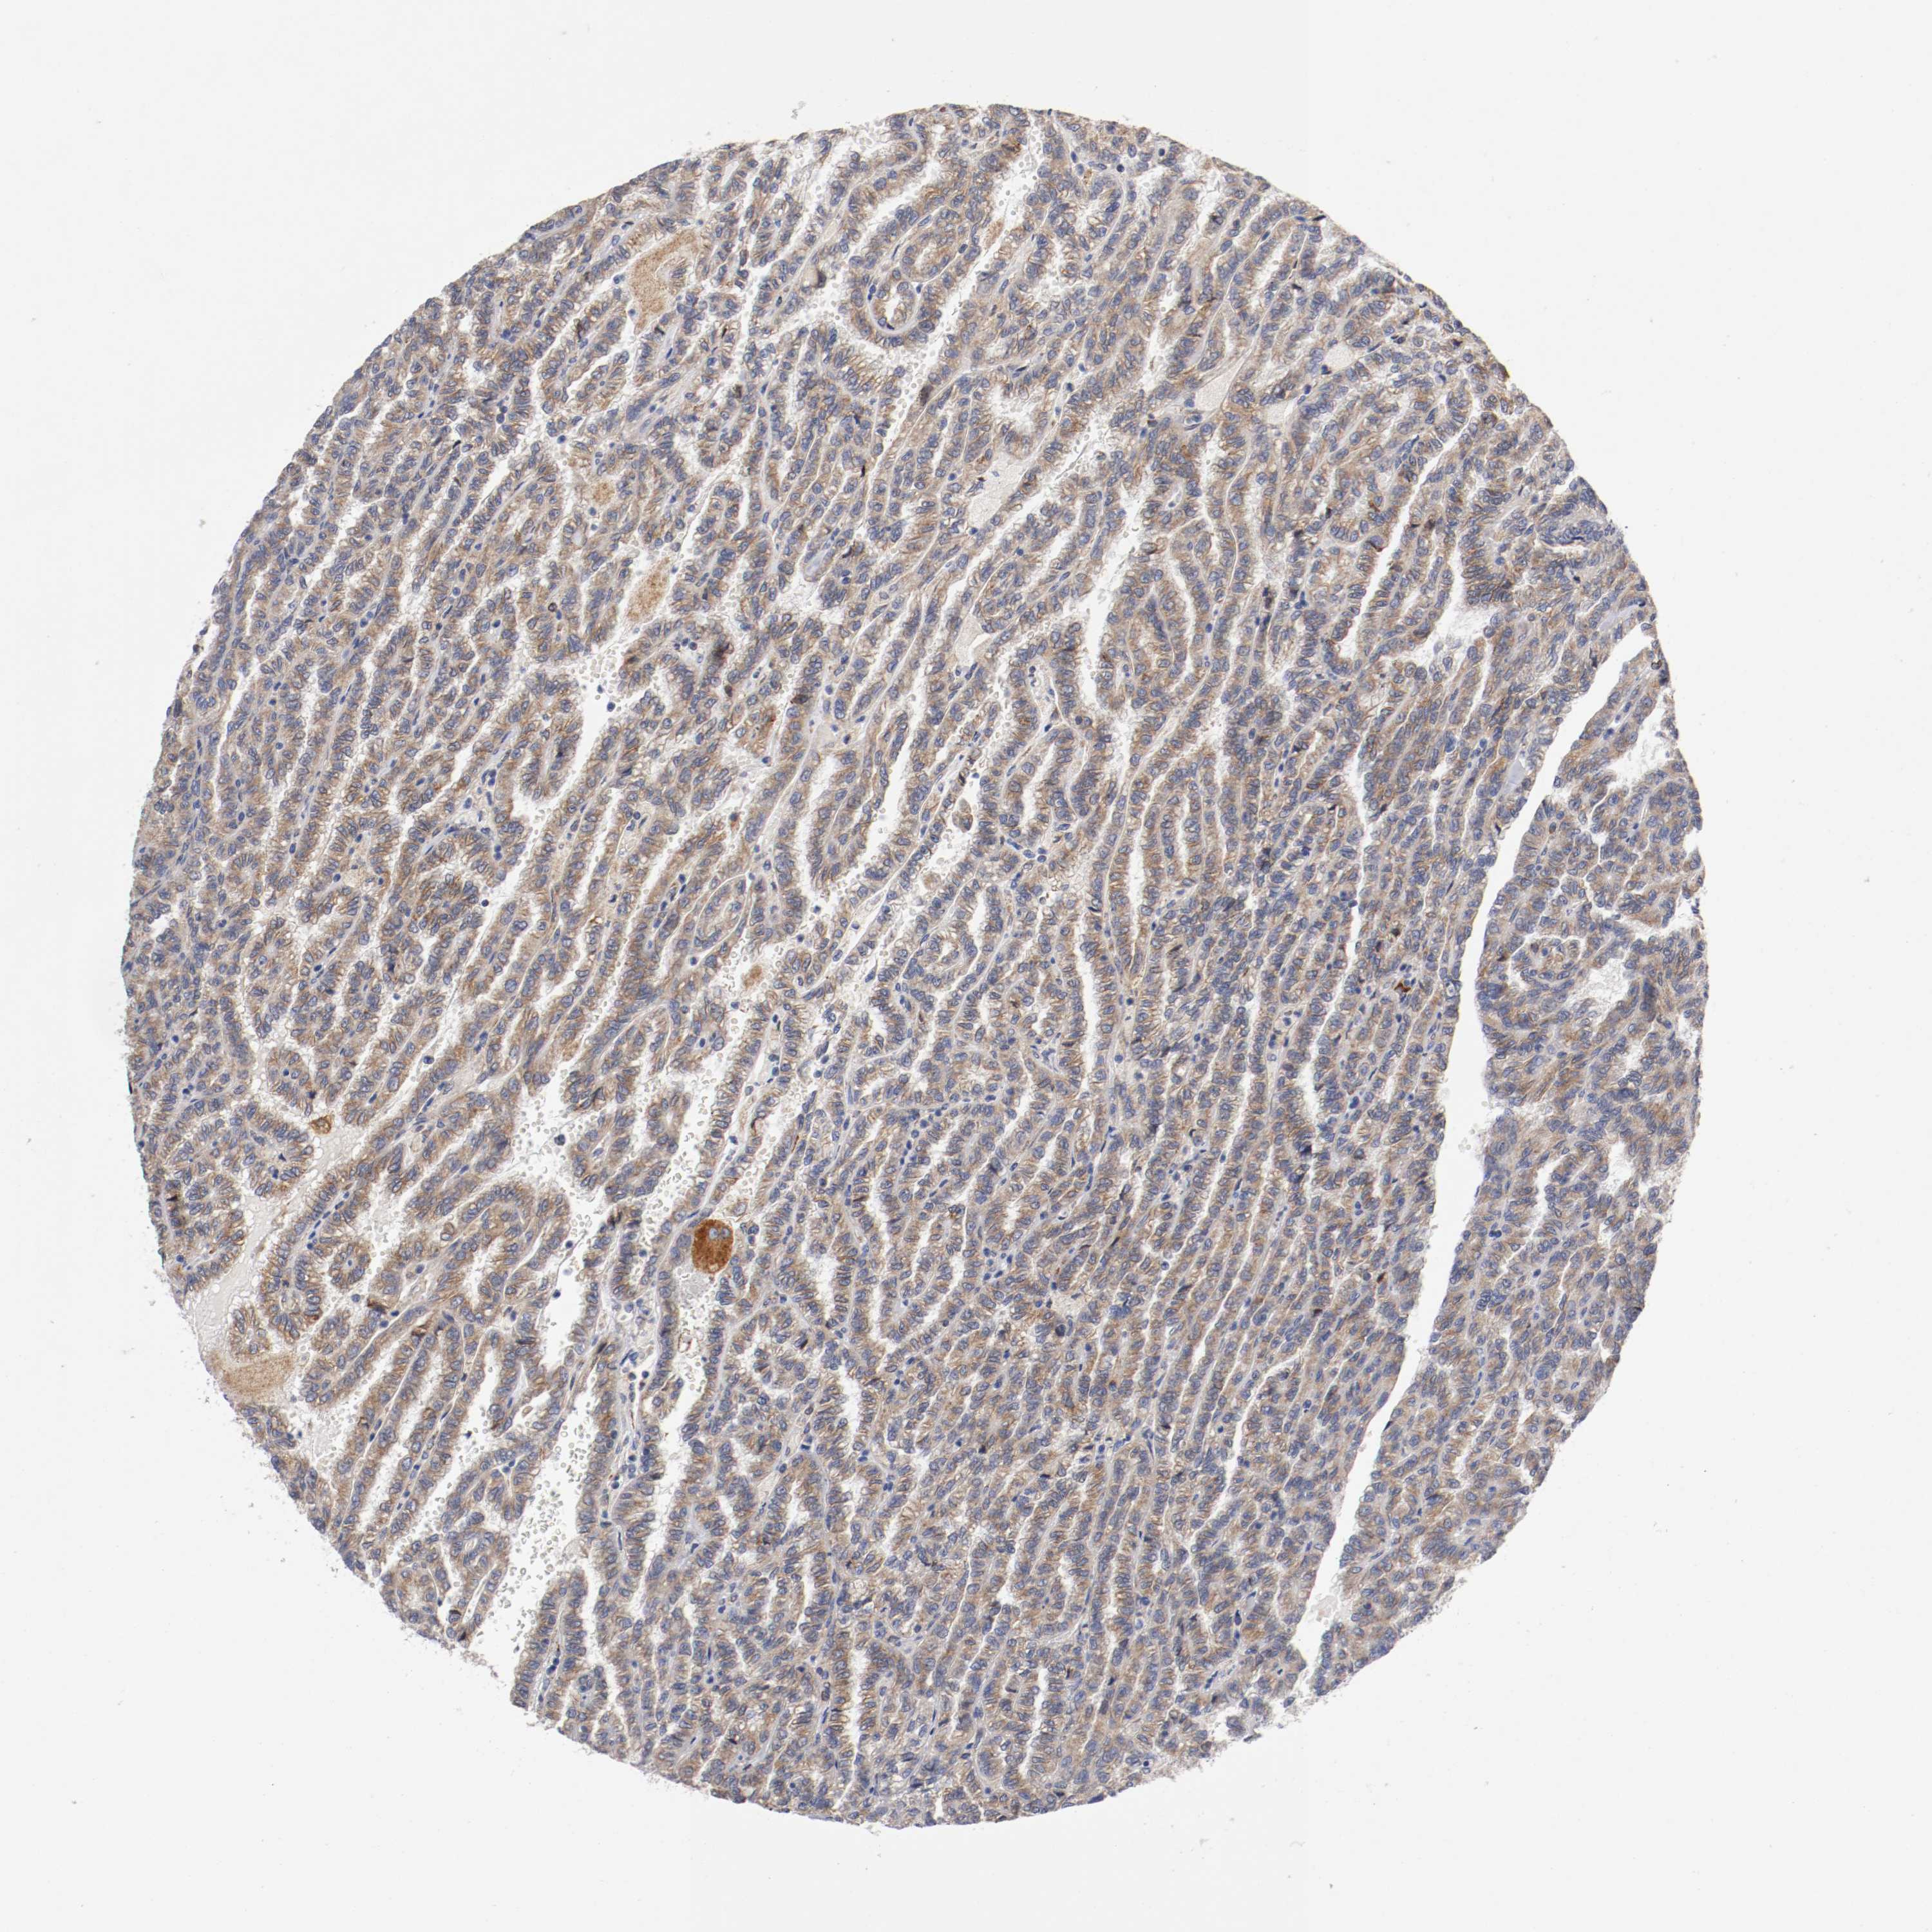

CANCER RENAL CANCER Show tissue menu

KICH TCGA KIRC TCGA KIRC VALIDATION KIRP TCGA PROTEIN RCC CPTAC PROTEIN EXPRESSION

Kidney renal papillary cell carcinoma